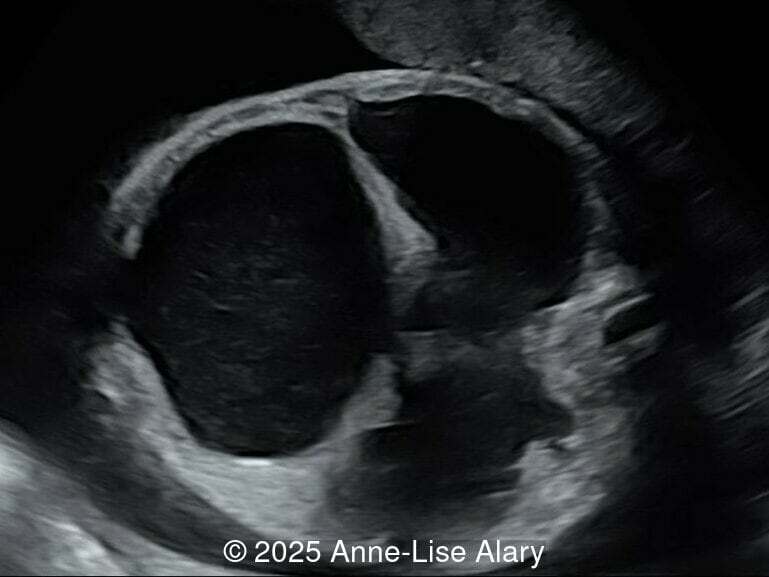

Image 3 Axial image of the abdomen

Our prenatal ultrasound revealed a male fetus with megabladder, dilation of both ureter and kidneys, and thinned kidney parenchyma consistent with Lower Urinary Tract Obstruction (LUTO).  Additional findings suspected on ultrasound and confirmed on computed tomography included:

The diagnosis of PBS is often made in the second trimester of pregnancy, although it has been described as early as 11 weeks of gestation [20]. The most frequent ultrasound findings are a large, thin-walled bladder accompanied by bilateral hydroureter/hydronephrosis, dysplastic kidneys with echogenic renal parenchyma and renal cortical cysts, and abdominal wall laxity which is better viewed after bladder decompression [21]. Cryptorchidism can be detected prenatally by 28 to 30 weeks gestation when the testes descend into scrotum. There may be a patent urachus, visible as a cystic connection between bladder and umbilicus. Oligohydramnios is a frequent finding, which makes it difficult to visualize the associated anomalies.